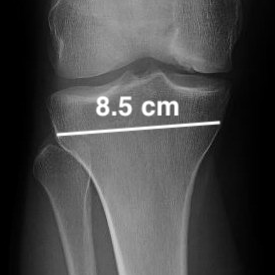

Example of 5 degree correction for medial cartilage procedure

- Opening height medially = tibial width X Tan angle correction required

- Wedge = 85 mm x tan 5 = 85 x 0.87 = 7 mm